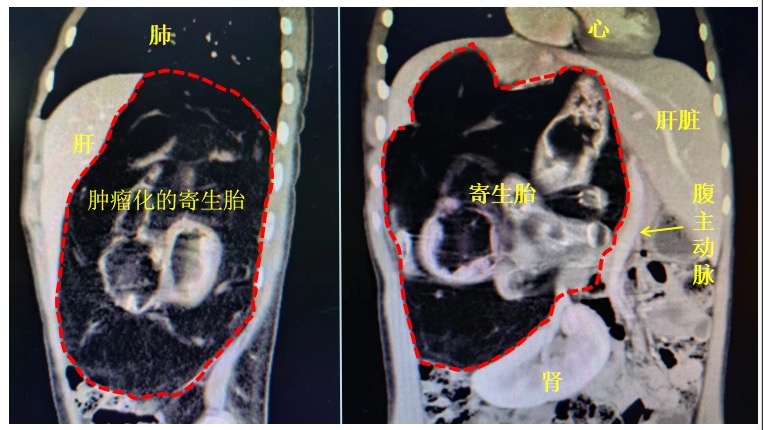

在省中医院胃肠肿瘤中心,小邱接受了各项检查。术前CT提示,小邱的肿瘤位于右上腹腹膜后,考虑为罕见的体内巨大寄生胎,位于右肝后方的腹膜后区域,直径达25厘米。 寄生胎是一种世界罕见的先天性疾病,遗传学上又称“胎中胎”,发病率约为五十万分之一。目前,全球相关文献中仅报道200余例。

检查发现,由于该寄生胎早已死亡,呈肿瘤性生长。肿瘤将下腔静脉向前包绕、推挤达前腹壁附近,将腹主动脉向左侧严重向左侧推挤。肝脏、右侧肾脏、膈肌、右肺都受到了严重挤压,右肺功能也受到损害。

最具有挑战性的是,肿瘤与器官之间没有任何分界线,手术极有可能损伤腹主动脉或者下腔静脉导致大出血而死亡。而肝门区和肾门区的解剖分离也是极为困难的,随时都有可能出现不可预测的致命事件。

CT图像提示肿瘤被多个重要脏器重重包裹